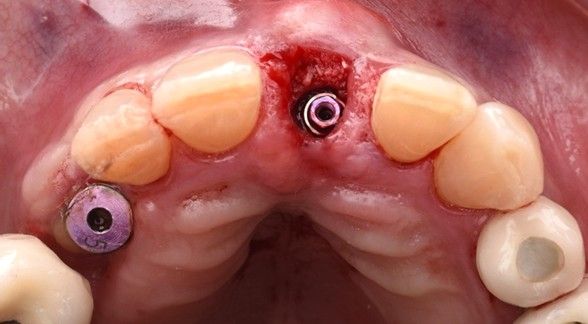

Bajo anestesia local mediante articaína al 4 % con epinefrina 1:100.000 (Ultracain®), se realizó una exodoncia atraumática utilizando mini luxadores, con el objetivo de preservar al máximo los tejidos duros y blandos (Figura 3). Tras la extracción, el alveolo fue cuidadosamente legrado y desinfectado mediante irrigación secuencial con peróxido de hidrógeno al 1,5%, clorhexidina al 0,20 % y suero salino estéril.

Posteriormente, siguiendo el protocolo de fresado recomendado por el fabricante, se colocó un implante de conexión interna (Klockner Vega Plus®3,6 × 12 mm) (Figura 4), alcanzándose un torque de inserción de 45 N/cm, lo que permitió la realización de una restauración provisional fija inmediata.

El implante se posicionó aproximadamente 4 mm subgingival en sentido vertical y manteniendo un gap vestibular superior a 2 mm en sentido horizontal (Figura 5). Dicho espacio fue rellenado con un xenoinjerto óseo de origen bovino (Bio-Oss®, Geistlich). A continuación, se realizó un injerto de tejido conectivo, obtenido de la tuberosidad maxilar, mediante una técnica de túnel en la zona vestibular, fijándolo con sutura reabsorbible incolora 5/0 (Monocryl Plus, Ethicon®) (Figura 6).